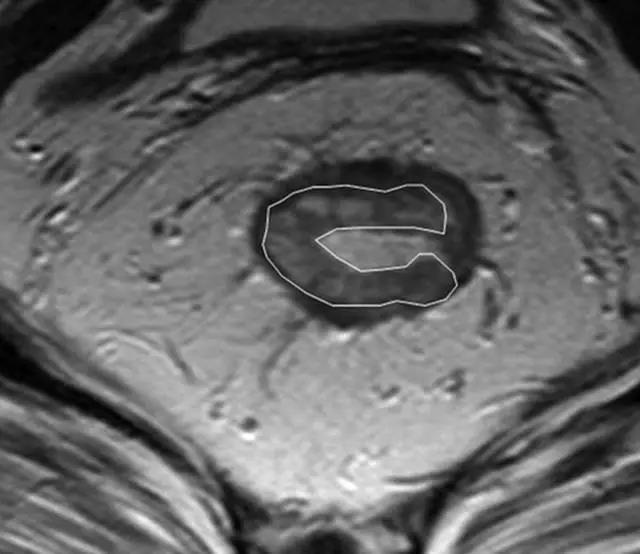

62 岁直肠癌妇女,薄层 T2 加权轴位 MR 图像显示直肠癌,在 9 点钟位置。

箭头显示直肠系膜筋膜。

MR 图像的示意图。